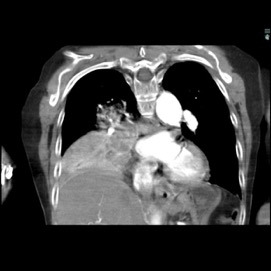

The patient was a 40-year-old white woman with a medical history significant for asthma, obstructive sleep apnea, and Down syndrome and who presented with dyspnea and fevers up to 102°F. She had recently completed an outpatient course of azithromycin, but she presented to an outside hospital for worsening shortness of breath despite this therapy. At the outside hospital, a computed tomography (CT) scan of the chest revealed a 3.7-cm heterogeneously enhancing mass that obstructed the bronchus intermedius with right middle and lower lobe consolidation (Figure 1a). The coronal thoracic CT scan demonstrated right middle and lower lobes that were atelectatic and consolidated with extensive and diffuse secondary mucous plugging (Figure 1b). Laboratory examination results at this time were significant for a white blood cell count 16.5x103/µL, sodium level of 133 mEq/L, potassium level of 3.2 mEq/L, serum creatinine level of 0.54 mg/dL, calcium level of 11.7 mg/dL, and lactic acid level of 2 mmol/L. She was transferred to the presenting institution for further evaluation and management.